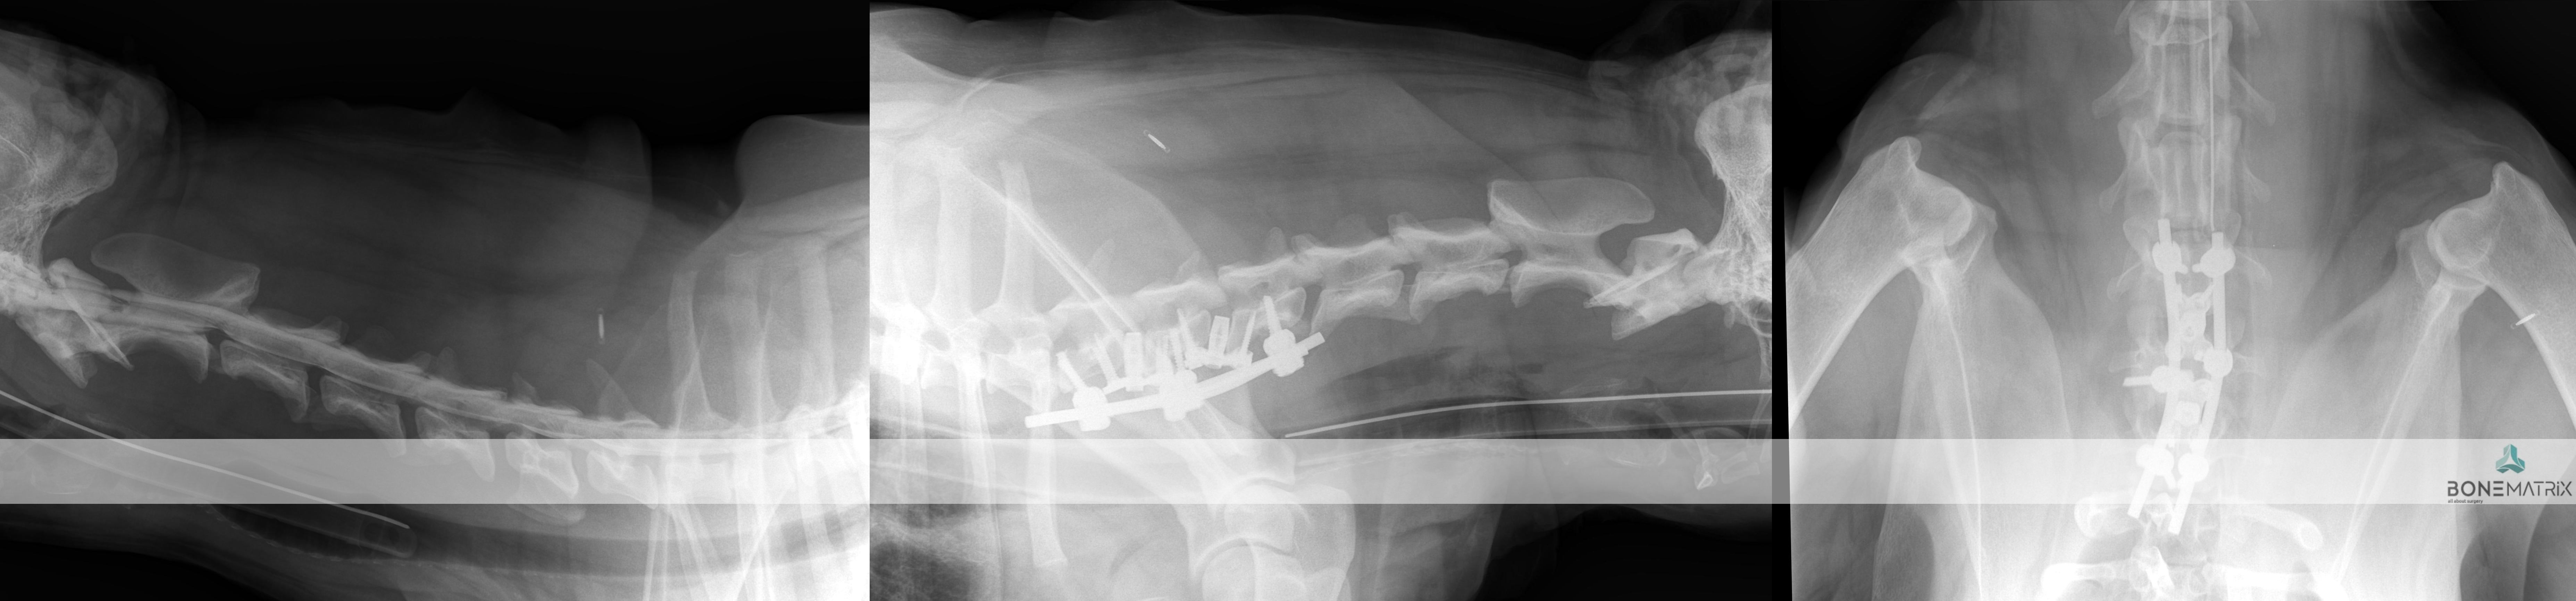

O que é?

O síndrome de Wobbler também designado por espondilomielopatia cervical é uma causa comum de patologia compressiva de medula em cães de raça grande a gigante.

Em qualquer uma das apresentações da doença existe um efeito compressivo sobre a medula espinal localizado nas vertebras cervicais.

Que apresentações pode assumir esta doença?

O síndrome de Wobbler pode ter uma apresentação onde a compressão é consequência de uma proliferação óssea a nível das vertebras e outra onde o efeito compressivo advém dos discos intervertebrais.

O diagnóstico é realizado com base em técnicas de imagem avançada (TAC ou RM).

Qual o tratamento indicado?

O tratamento aconselhado para a resolução destes casos é a descompressão medular por meio da realização de uma técnica cirúrgica denominada por Ventral Slot.

Esta patologia caracteriza um quadro de subluxação atlanto-axial (entre as vertebras C1 e C2). Nesta patologia existe um fenómeno de compressão medular provocado pela incapacidade destas vertebras articularem normalmente.

O único tratamento possível é cirúrgico. Nesta cirurgia é realizada a fusão vertebral entre C1 e C2, resolvendo assim o seu problema de instabilidade primário. Nesta cirurgia as vertebras em causa são preparadas para serem estabilizadas de forma a que no pós cirúrgico exista uma união entre ambas formando uma única coluna óssea e estabilizando por consequência este segmento.